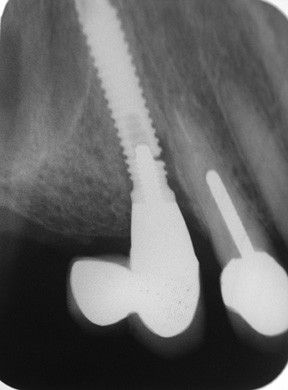

Для этого нами были изучены непосредственные и отдаленные результаты лечения периимплантита у 17 пациентов пародонтологического кабинета хирургического отделения АУЗ «РСП» в возрасте 24—56 лет (9 мужчин и 8 женщин) — основная группа — и 5 пациентов контрольной группы. Срок пользования имплантатами от 1 года до 7 лет, имплантаты как во фронтальных участках, так и в области премоляров и жевательных зубов (всего 24 имплантата). Не все пациенты обратились с жалобами (кровоточивость, отделяемое из десны, дискомфорт), у 5 пациентов (29,4±0,7 %) периимплантит был диагностирован во время осмотра. Диагноз периимплататный мукозит — у 2 пациентов, у остальных периимплантит, подтвержденный рентгенологически (рис. 1, 2) .

Рис. 1. Рентгенологическая картина периимплантита.

Рис. 2. Рентгенологическая картина периимплантита.